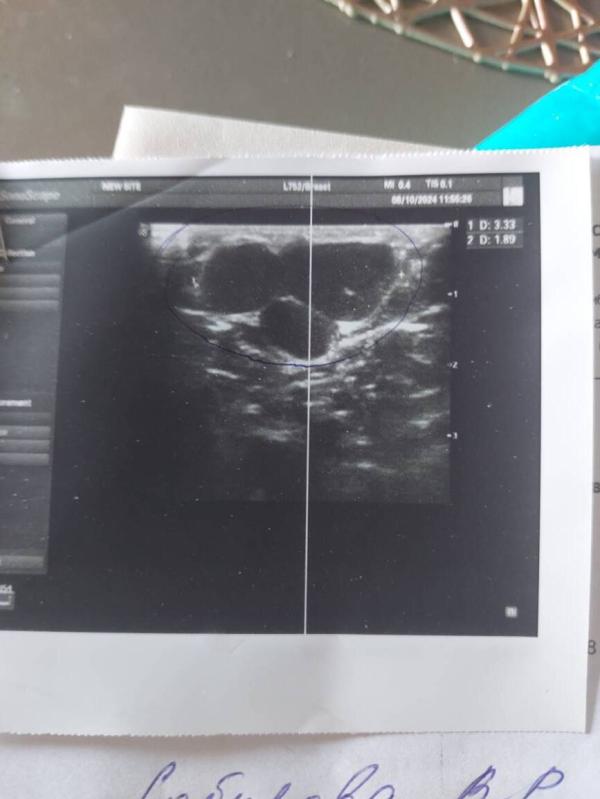

Просто на снимке узи получается, что она не одна